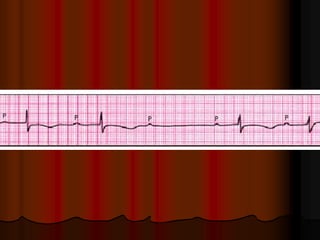

ЭКГ

Обычно отмечаются преходящие неспецифические

изменения сегмента ST и зубца T. Нередко у больных

острым миокардитом регистрируются патологические зубцы

Q и уменьшение амплитуды зубцов R в правых грудных

отведениях (V1-V4). Поскольку в острой фазе миокардита

активность сердечных изоферментов обычно повышена, это

в совокупности с указанными изменениями ЭКГ может

повлечь ошибочный диагноз инфаркта миокарда. Часто

встречаются желудочковая и наджелудочковая

экстрасистолия, реже - нарушения атриовентрикулярной

проводимости. Эпизоды мерцательной аритмии, а также

блокады ножек пучка Гиса (чаще левой),

свидетельствующие об обширности поражения миокарда,

указывают на неблагоприятный прогноз